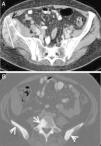

Mediante las imágenes biomédicas podemos diagnosticar, estadificar, controlar y valorar la efectividad de los procedimientos terapéuticos a los que son sometidos los pacientes oncológicos. RECIST (Response Evaluation Criteria In Solid Tumors) es el método para monitorizar el tratamiento mediante medidas unidimensionales de los tumores, obtenidas con técnicas de imagen reproducibles como son la TC, la RM y la PET. Los cambios metabólicos inducidos por los nuevos tratamientos modifican la biología y comportamiento del tumor, con discordancia ocasional entre el estado clínico del paciente y la respuesta medida con RECIST, lo que apunta a la necesidad de incluir pruebas funcionales en la valoración de la respuesta al tratamiento.

Biomedical imaging makes it possible not only to diagnose and stage cancer, but also to follow up patients and evaluate the response to treatment. RECIST (Response Evaluation Criteria In Solid Tumors) provides a method to monitor the response to treatment based on one dimensional measurements of tumors obtained with reproducible imaging techniques like CT, MRI, and PET. The metabolic changes induced by new treatments modify the biology and behavior of the tumor; occasionally, there is a discrepancy between the patient's clinical condition and the response measured by RECIST, which indicates that functional tests need to be included in the evaluation of the response to treatment.